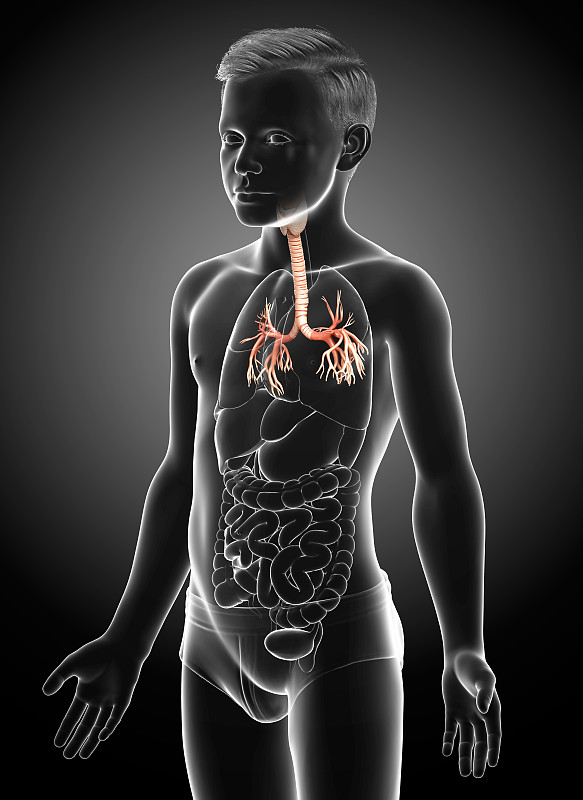

人体呼吸系统肺解剖详情

JPG